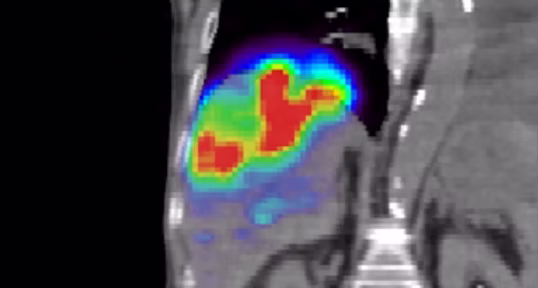

Taebi, A., Vu, C.T., Roncali, E. (2021).

Multiscale computational fluid dynamics modeling for personalized liver cancer radioembolization dosimetry.

ASME Journal of Biomechanical Engineering, 143(1): 011002.

honorable mention for the 2022 Skalak Award, among top 3 papers published by JBME in 2021 & 2022: 10.1115/1.4065051

Taebi, A., Pillai, R., Roudsari, B., Vu, C., Roncali, E. (2020).

Computational modeling of the liver arterial blood flow for microsphere therapy: Effect of boundary conditions.

Bioengineering, 7(3): 64.

Roncali, E.,Taebi, A., Roudsari, B.S., Vu, C.T. (2020).

Personalized dosimetry for liver cancer radioembolization based on computational fluid dynamics.

Annals of Biomedical Engineering, 48(5): 1499-1510.

Taebi, A., Vu, C.T., Roncali, E. (2020).

Prediction of Blood Flow Distribution in Liver Radioembolization Using Convolutional Neural Networks.

ASME International Mechanical Engineering Conference and Exposition, Portland, OR, V005T05A036.

Estimation of Yttrium-90 Distribution in Liver Radioembolization using Computational Fluid Dynamics and Deep Neural Networks.

IEEE Engineering in Medicine and Biology Society, Montreal, QC, Canada, pp. 4974-4977.

Taebi, A., Costa, G.C.A., Roncali, E. (2021).

Personalized dosimetry for brain cancer radioembolization: A feasibility study.

Roncali, E., Taebi, A., Spencer, B., Costa, G.C.A., Rusnak, M., Caudle, D., Roudsari, B., Pillai, R., Foster, C., Vu, C. (2020).

Comparison of Y-90 liver dose distribution predicted with fluid dynamics with Y-90 PET.

Journal of Nuclear Medicine 61 (supplement 1): 1308.

Roncali, E., Taebi, A., Rusnak, M., Spencer, B., Caudle, D., Foster, C., Vu, C.T. (2019).

Personalized dosimetry for liver cancer radioembolization using computational fluid dynamics.

European Journal of Nuclear Medicine and Molecular Imaging 46 (Suppl 1): S134.

Taebi, A., Roudsari, B.S., Vu, C., Cherry, S.R., Roncali, E. (2019).

Hepatic arterial tree segmentation: Towards patient-specific dosimetry for liver cancer radioembolization.

Journal of Nuclear Medicine 60 (supplement 1) 122.